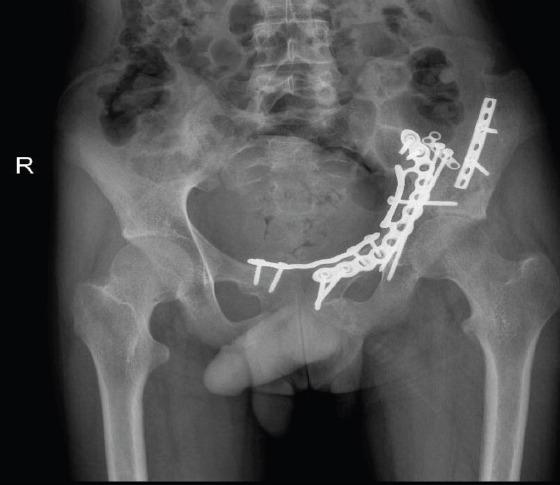

在此,我们报告一例16岁男性,有道路交通事故史,单纯闭合性左髋臼骨折。X线显示双侧髋臼柱骨折伴中心性半脱位。通过改良的Stoppa入路并带有外侧窗口对其进行切开复位内固定治疗。患者在受伤后第6天接受了ORIF。使用钢板和螺钉进行固定。在恢复室,他整个左上肢无法活动且无感觉,而手术肢体的远端神经血管功能正常。恢复15分钟后,感觉恢复,但运动功能障碍持续存在,提示臂丛神经失用。进行了脑部CT扫描,结果未见异常。6个月后,患者自行恢复了感觉,左上肢力量改善至5/5。